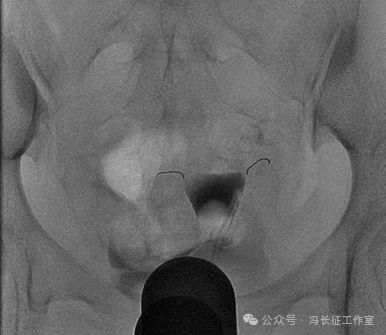

2014年5月在DSA上行输卵管近段介入栓塞术

栓塞前造影也显示双侧输卵管间质部和峡部细长,适合栓塞。于是向双侧输卵管间质部和峡部各栓塞一枚3/2(长2厘米,一端直径小2毫米另一端直径大是3毫米,就是向宝塔一样,有时被称为塔圈)弹簧圈。

微信图片_20240223171147(2).jpg